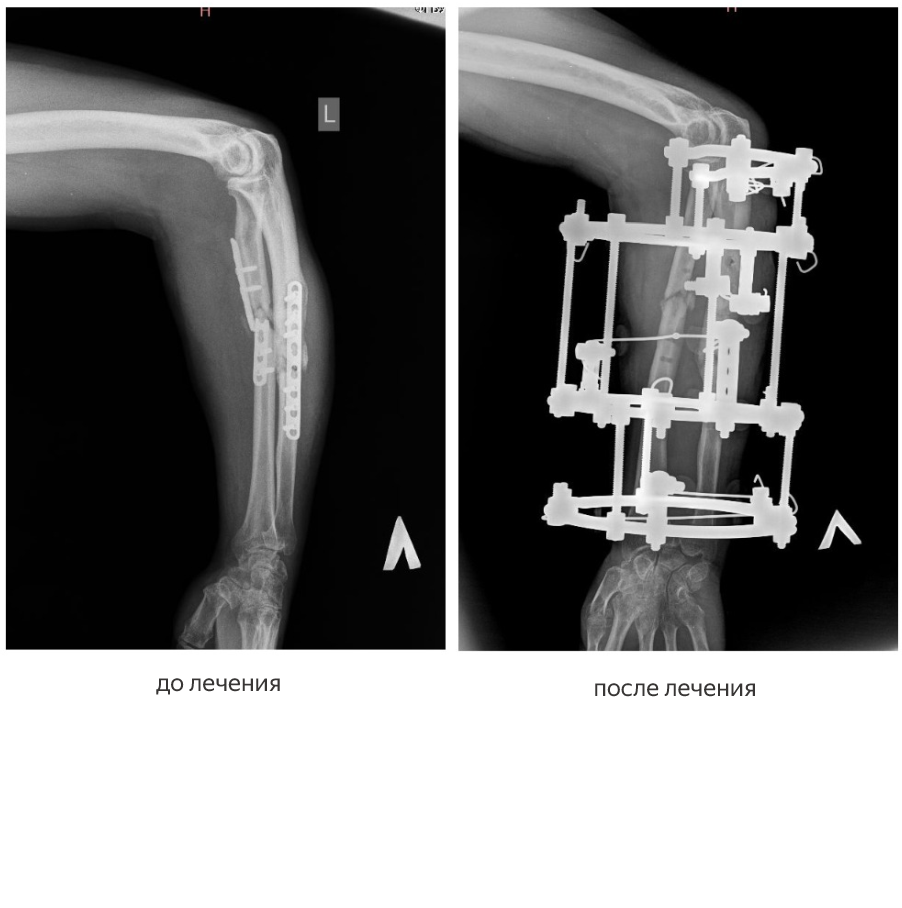

Первый пациент — участник специальной военной операции — поступил в центр с диагнозом «ложные суставы лучевой и локтевой костей предплечья». Лечение проходило в два этапа.

Как рассказал заведующий отделением № 3, врач-травматолог-ортопед высшей категории Виталий Нарицын, в декабре 2025 года мужчине удалили ранее установленные сломанные накостные пластины и выполнили остеосинтез аппаратом Илизарова.

«Эта операция носила подготовительный характер: пластины располагались с ладонной поверхности предплечья, их удаление осложнялось большим массивом мягких тканей, к тому же сами пластины были сломаны, — пояснил Виталий Нарицын. — Мы удалили пластины и зафиксировали предплечье аппаратом Илизарова, чтобы обеспечить заживление раны и подготовить конечность ко второму этапу оперативного лечения».

Второй этап прошел в марте 2026 года. Хирурги перепровели элементы фиксации, выполнили перемонтаж аппарата и полностью восстановили правильную ось лучевой и локтевой костей. Сейчас пациент выписан на амбулаторное лечение по месту жительства. По оценке врачей, кости стабильно зафиксированы, ось конечности правильная.